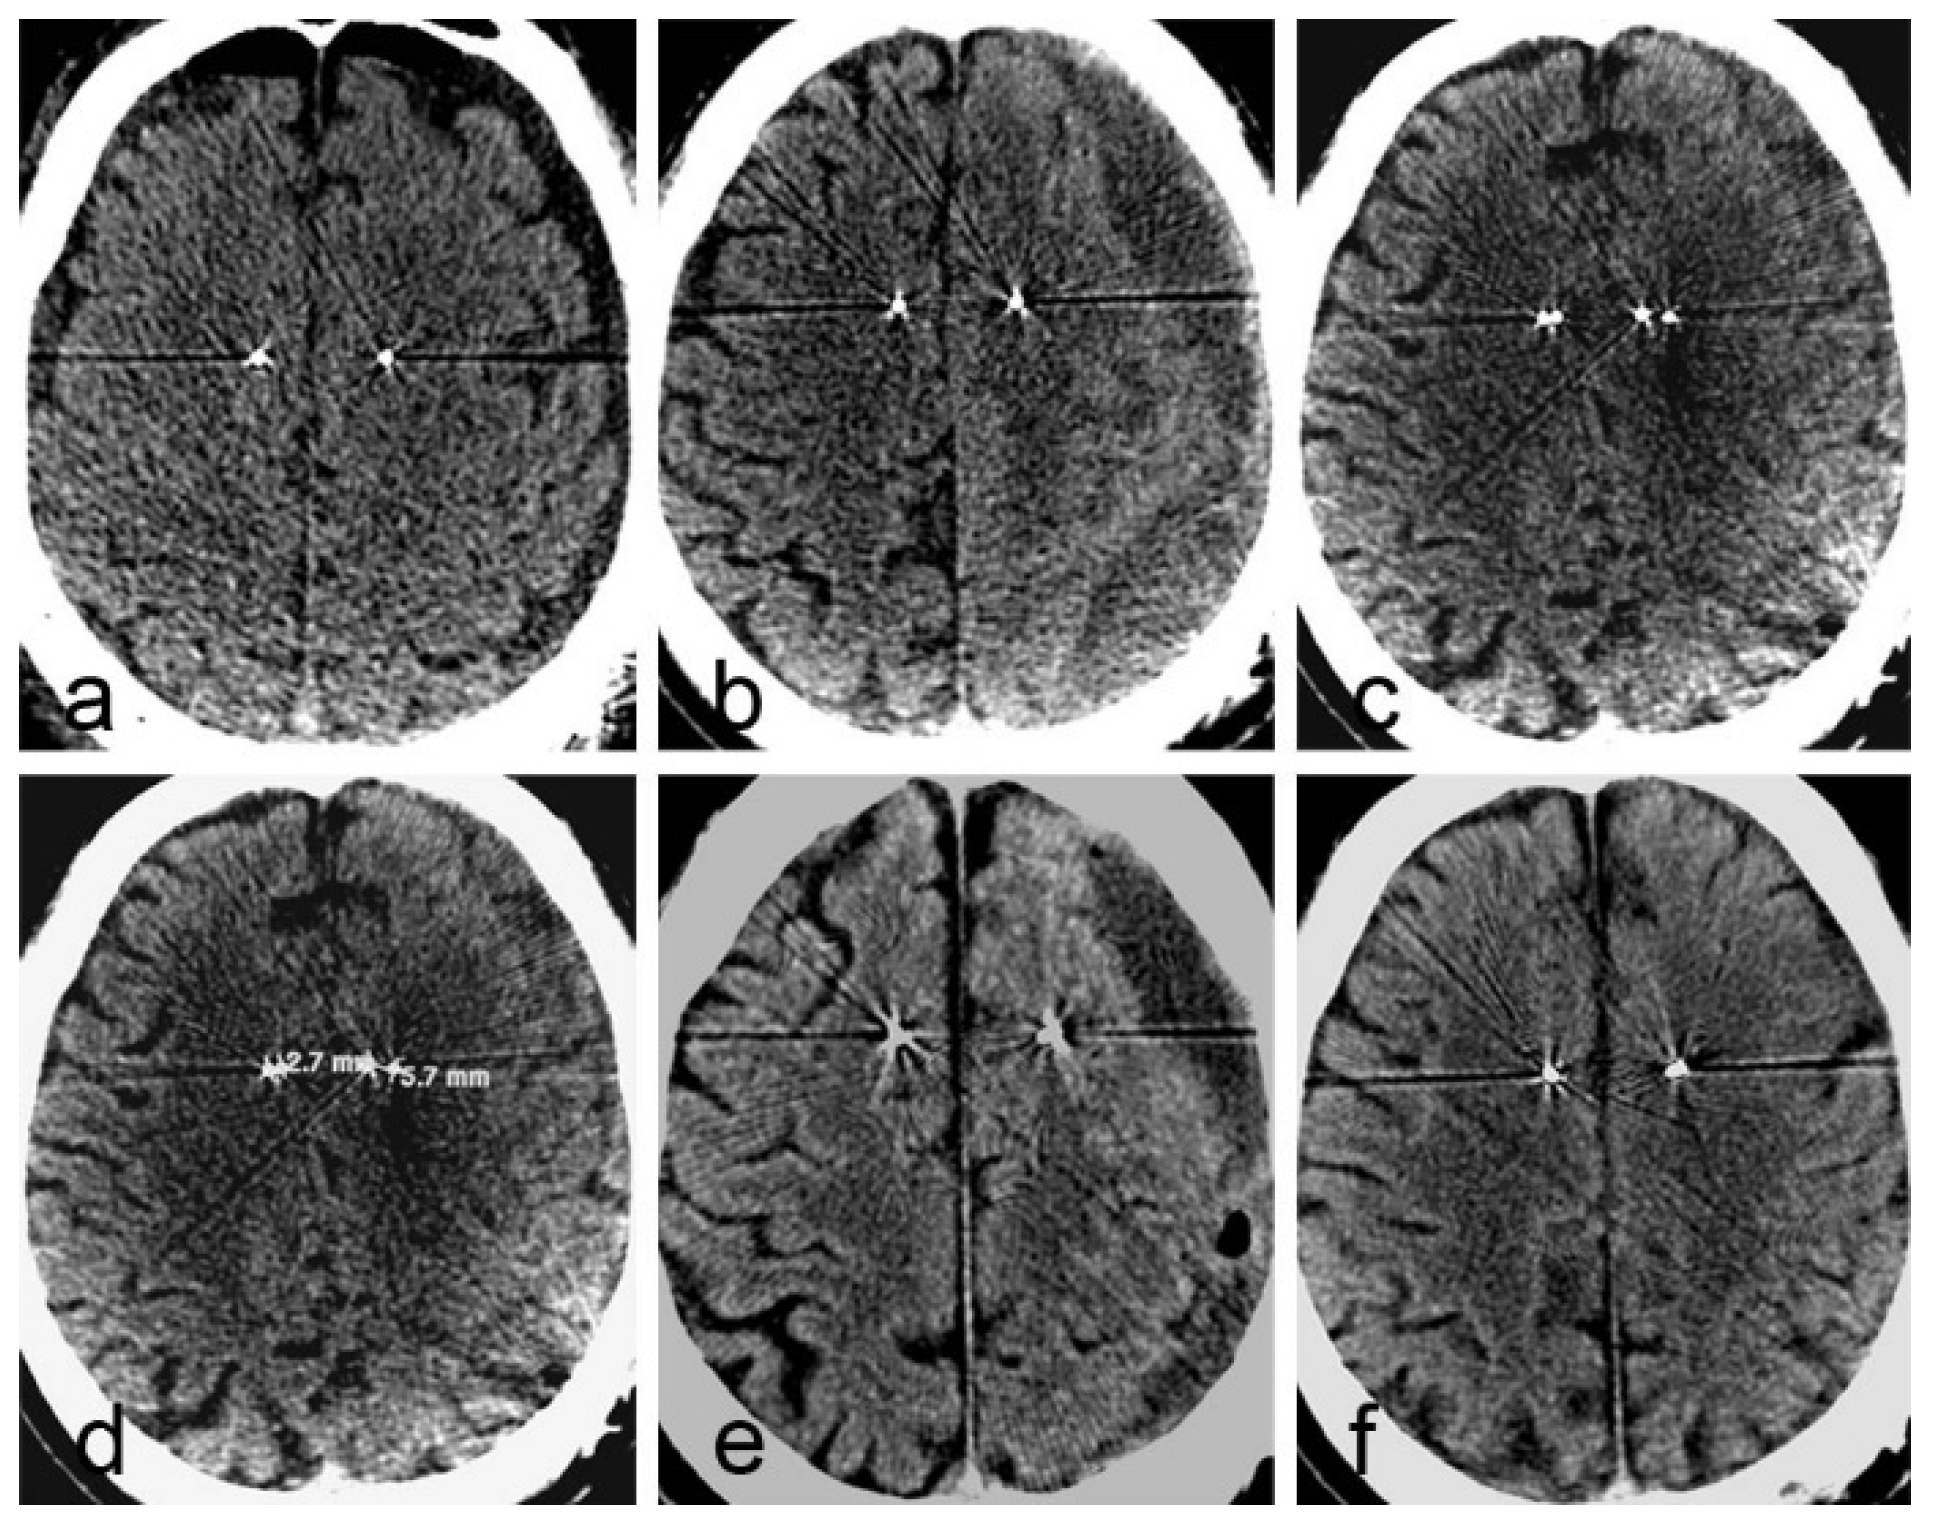

2.1. Case 1

2.2. Case 2

| Case 1 | 62 | F | Parkison’s disease | GPI | Yes | Yes | 36 days | description | poor |

| Case 2 | 56 | M | Alzheimer’s disease | fornix | Yes | Yes | 49 days | description | poor |